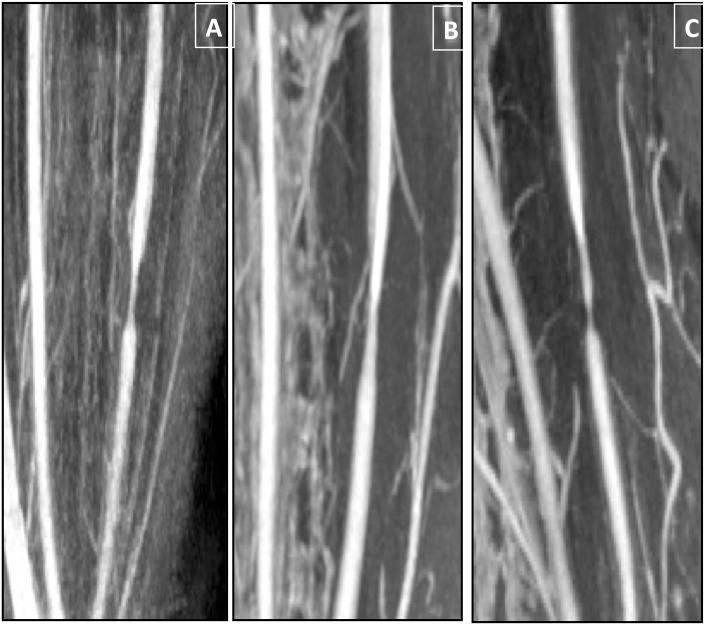

A surgical procedure was performed to create left common carotid artery stenosis by placement of a perivascular cuff in minipigs under atherogenic diet. Animals were followed up on 3T MRI, 1 week after surgery and 3, 6, and 8 months after initiation of the diet. Computational fluid dynamics simulation estimated WSS distribution for the first imaging point. Vascular geometries were co-registered for direct comparison of plaque development and features (Gadolinium- and USPIO-Contrast Enhanced MRI, for permeability and inflammation respectively) with the initial WSS. Histological analysis was performed and sections were matched to MR images, based on spatial landmarks.

Vessel wall thickening, permeability and inflammation were observed distally from the stenosis. They were eccentric and facing regions of normal wall thickness. Histological analysis confirmed eccentric plaque formation with lipid infiltration, intimal thickening and medial degradation. High phagocytic activity in the stenosis region was co-localized with high WSS, corresponding to intense medial degradation observed on histology samples.

在狭窄远端观察到血管壁增厚、通透性增加和炎症。这些变化呈偏心性,且位于正常壁厚区域。组织学分析证实形成了偏心性斑块,伴有脂质浸润、内膜增厚和中膜退变。狭窄区域的高吞噬活性与高WSS共定位,这与组织学样本上观察到的强烈中膜退变相对应。